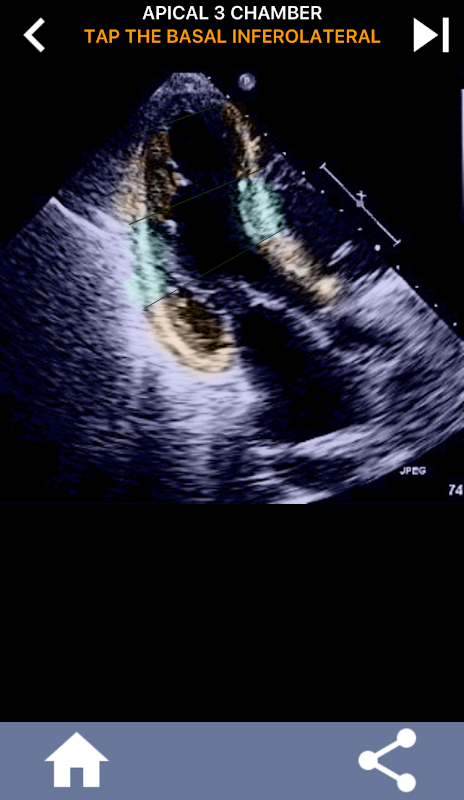

Questa app contiene tutte le viste eco che mostrano il miocardio segmentato AHA e ti chiede di toccare il segmento corretto. Personalmente trovo che il quiz ripetitivo funzioni al meglio per me quando ho bisogno di imparare / memorizzare rapidamente l'argomento. Se sei uno studente di ecografia che studia eco / TTE, penso che questo sarebbe un eccellente complemento ai tuoi studi.